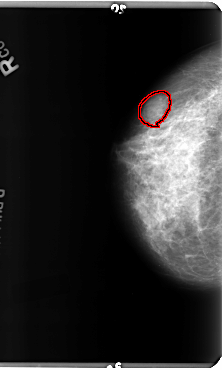

B_3156_1.RIGHT_CC

RIGHT_CC LINES 4800 PIXELS_PER_LINE 2880 BITS_PER_PIXEL 12 RESOLUTION 50 OVERLAY

FILE: B_3156_1.RIGHT_CC.OVERLAY

TOTAL_ABNORMALITIES 1

ABNORMALITY 1

LESION_TYPE MASS SHAPE OVAL MARGINS CIRCUMSCRIBED-OBSCURED-ILL_DEFINED

ASSESSMENT 4

SUBTLETY 3

PATHOLOGY BENIGN

TOTAL_OUTLINES 1

BOUNDARY